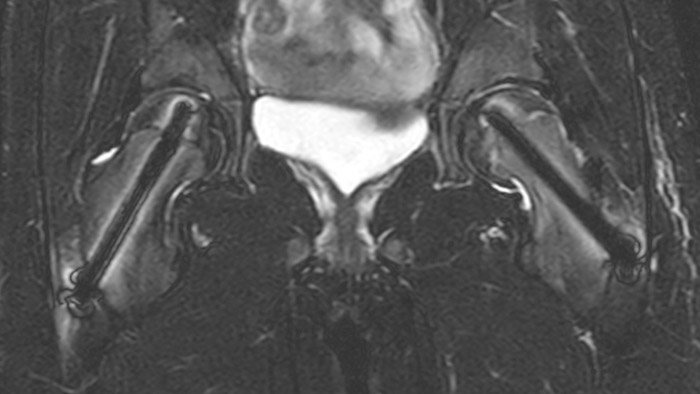

After intervention with two cannulated titan screws, it is important to check that the circumference is normal and without necrosis. The screws can cause major metal artifacts, but O-MAR allows to improve visualization of tissue and bone in the near vicinity of MR Conditional orthopedic implants1. 1 Only for use with MR Safe or MR Conditional implants by strictly following the Instructions for Use